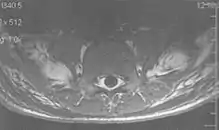

Flow can manifest as either an altered intravascular signal (flow enhancement or flow-related signal loss), or as flow-related artifacts (ghost images or spatial misregistration). Flow enhancement, also known as inflow effect, is caused by fully magnetised protons entering the imaged slice while the stationary protons have not fully regained their magnetization.[1] The fully magnetized protons yield a high signal in comparison with the rest of the surroundings. High velocity flow causes the protons entering the image to be removed from it by the time the 180-degree pulse is administered. The effect is that these protons do not contribute to the echo and are registered as a signal void or flow-related signal loss (Fig. 2).[1] Spatial misregistration manifests as displacement of an intravascular signal owing to position encoding of a voxel in the phase direction preceding frequency encoding by time TE/2.The intensity of the artifact is dependent on the signal intensity from the vessel, and is less apparent with increased TE.[1]